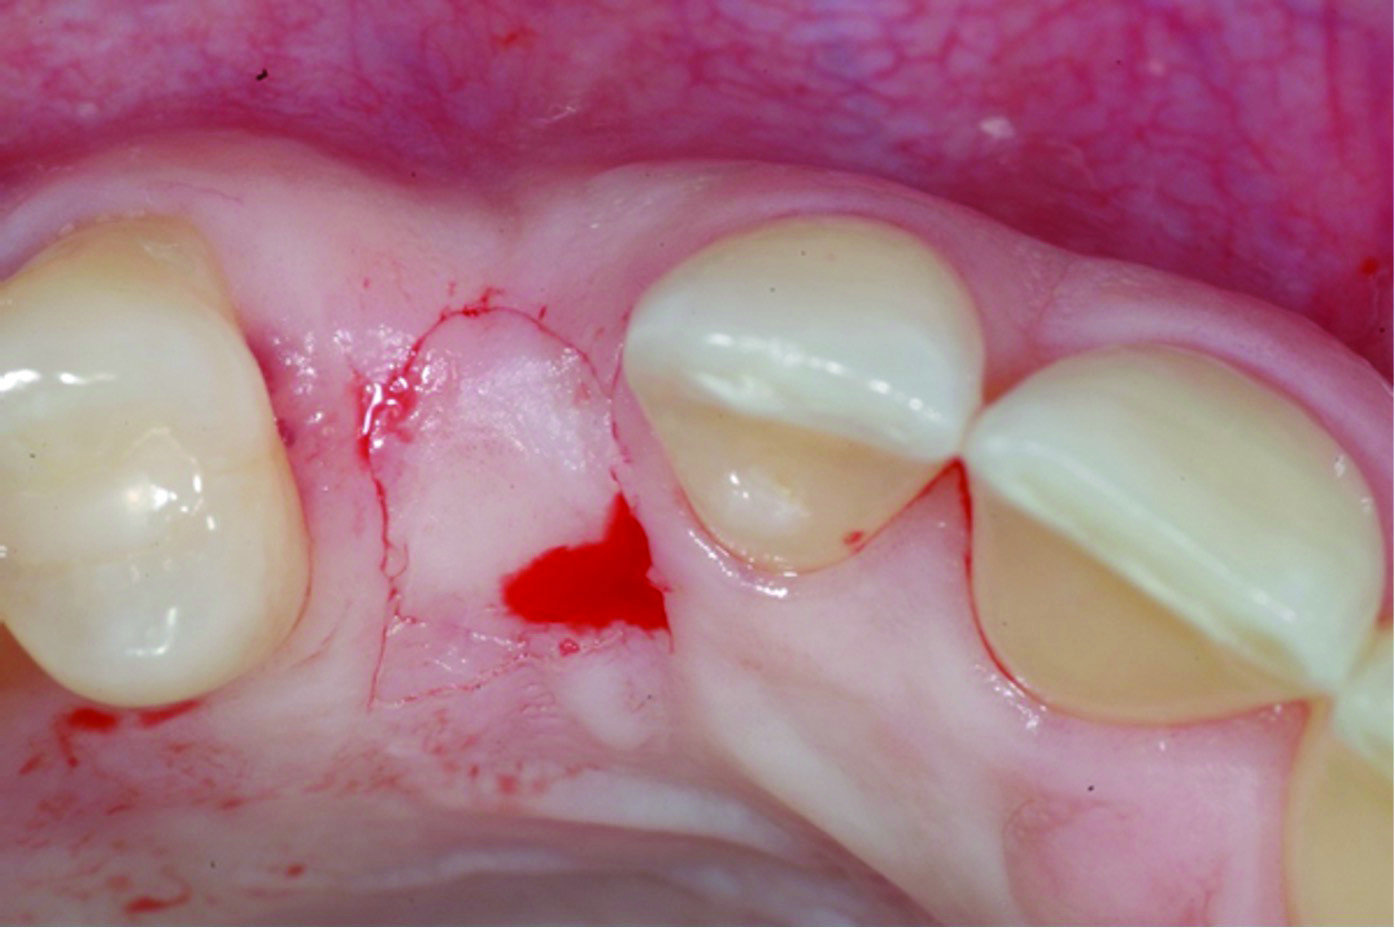

Fig 6 through Fig 8. Example of increasing KMW with an APF at implant uncovery. Fig 6: initial presentation showing lack of KMW; Fig 7: healing abutment placement with APF; Fig 8: 2 months post-treatment. (The dotted lines indicate the MGJ.) Fig 9 through Fig 11. Example of increasing KMW with an APF and FGG at implant uncovery.

Fig 9: initial presentation;